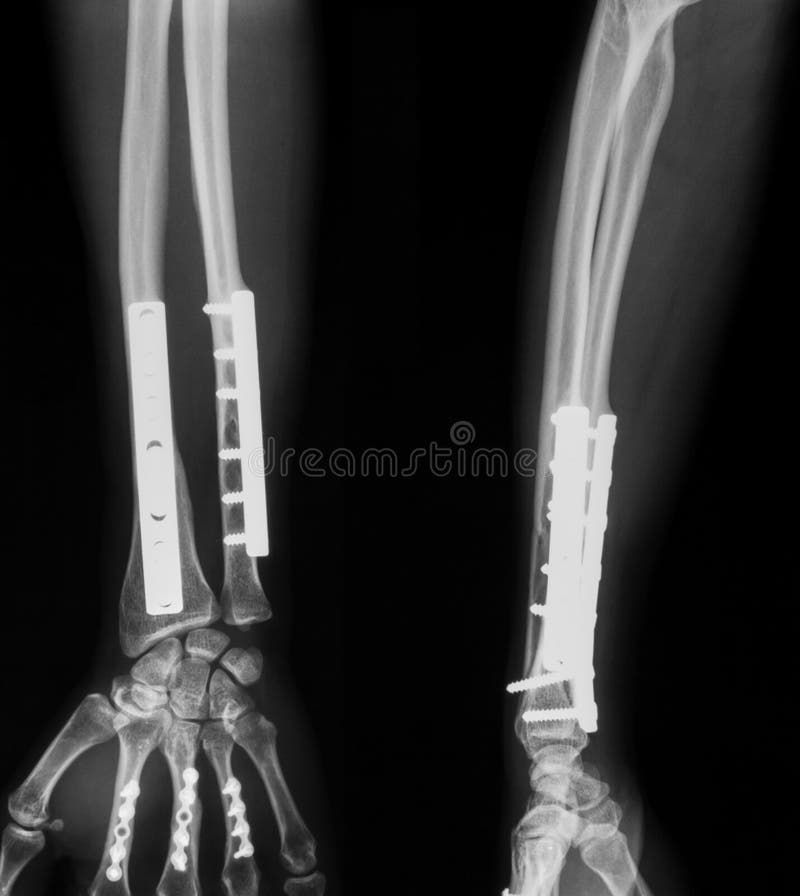

From de.dreamstime.com

Röntgenbild Des Gebrochenen Unterarms, Des AP Und Der Seitenansicht Arm Gebrochen Symptome Wie bei allen brüchen ist auch bei einem oberarmbruch das hauptsymptom der schmerz mit einer typischen schonhaltung. Eine fraktur des oberarms ist mit eindeutigen und typischen symptomen verbunden, sodass eine eigendiagnose oftmals sehr einfach ist. Die fraktur lässt sich häufig bereits optisch erkennen. Fehlstellung, sichtbare knochenfragmente bei offener fraktur. Es entsteht eine angeschwollene auswölbung und der unterarm knickt ab, was. Arm Gebrochen Symptome.